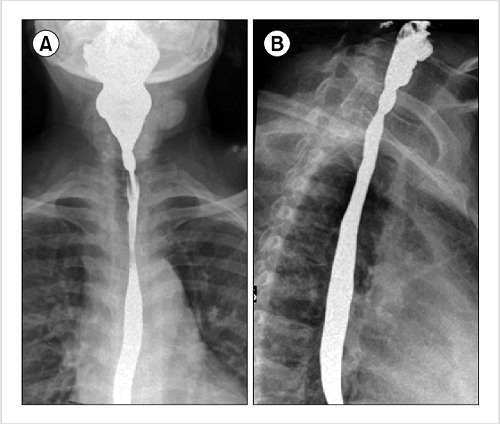

We were told to bring stuff for him to eat and drink, but they had an applesauce and crackers there for him. I had brought applesauce, fruit loops, and some other things for him. They mixed the barium with applesauce and I gave him a few spoons of that. Then we added fruit loops to it and he ate a bit more. Then they added some barium to his sippy cup and had him drink from it.

And just like that, the test was over. There was a doctor there monitoring things as the test was in progress. He told me that Andrew was not aspirating and all looked good. I was relieved. Since the test was over quicker than I anticipated, we walked to the food court and I bought us cookies!